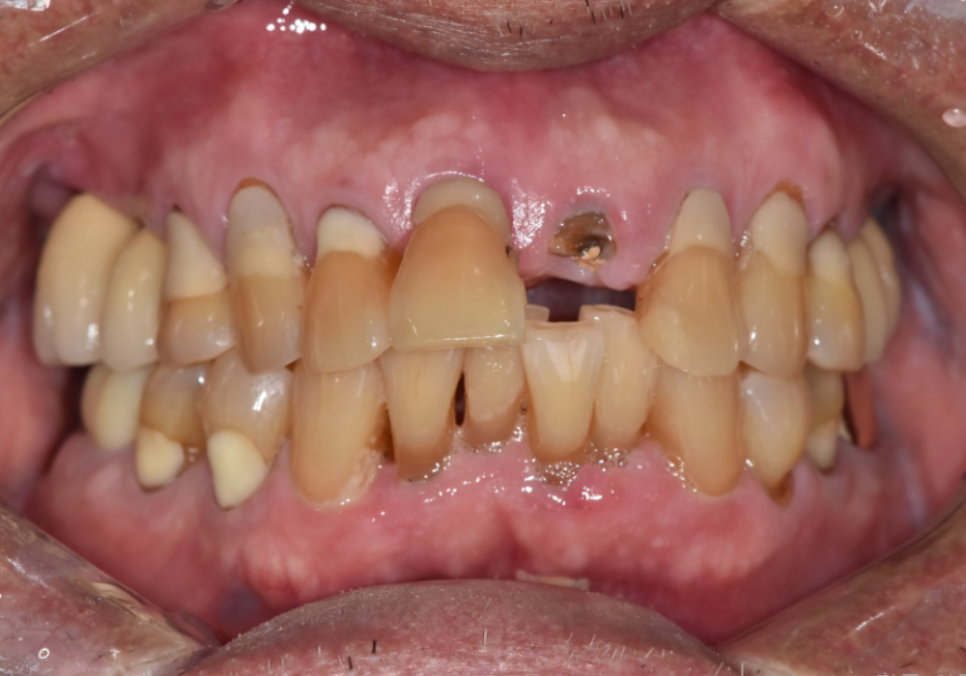

이 환자분은

왼쪽 앞니가 충치로 인해 부러지면서

내원하셨습니다.

250221

겉으로 보면

앞니 하나만 문제가 있어 보일 수 있지만,

입안을 자세히 살펴보니

앞니 4개 모두 흔들림이 있었고

잇몸뼈 높이도 많이 낮아져

있는 상태였습니다.